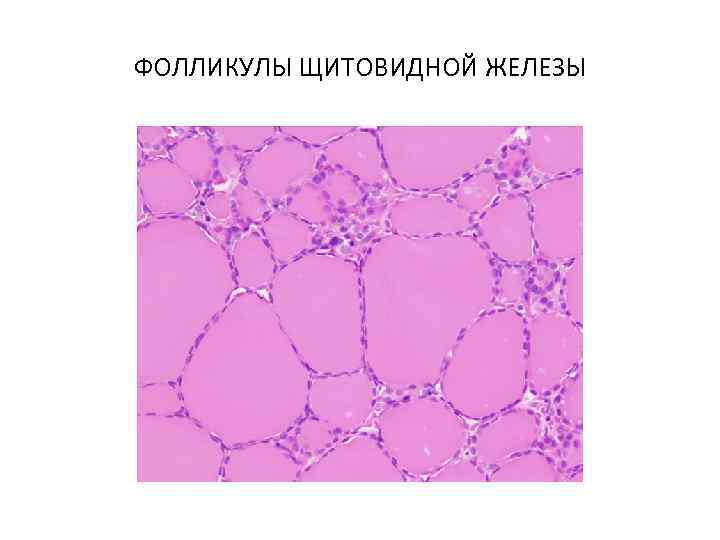

ФОЛЛИКУЛЫ ЩИТОВИДНОЙ ЖЕЛЕЗЫ

ФОЛЛИКУЛЫ ЩИТОВИДНОЙ ЖЕЛЕЗЫ